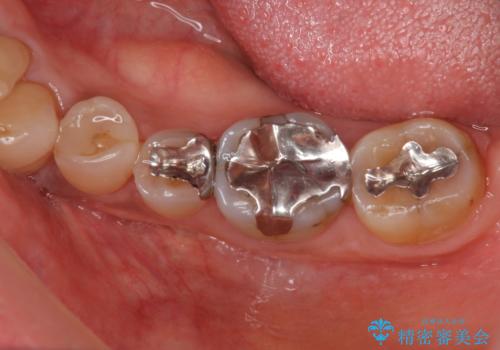

臼歯 咬合の再構成

- 20年前に治療した銀歯が壊れ、審美的な修復を希望され来院されました。

銀歯・虫歯を除去し、ジルコニアを咬合再構成を行います。

- 66万円(仮歯・ジルコニアクラウン×6)費用は治療当時の料金となります